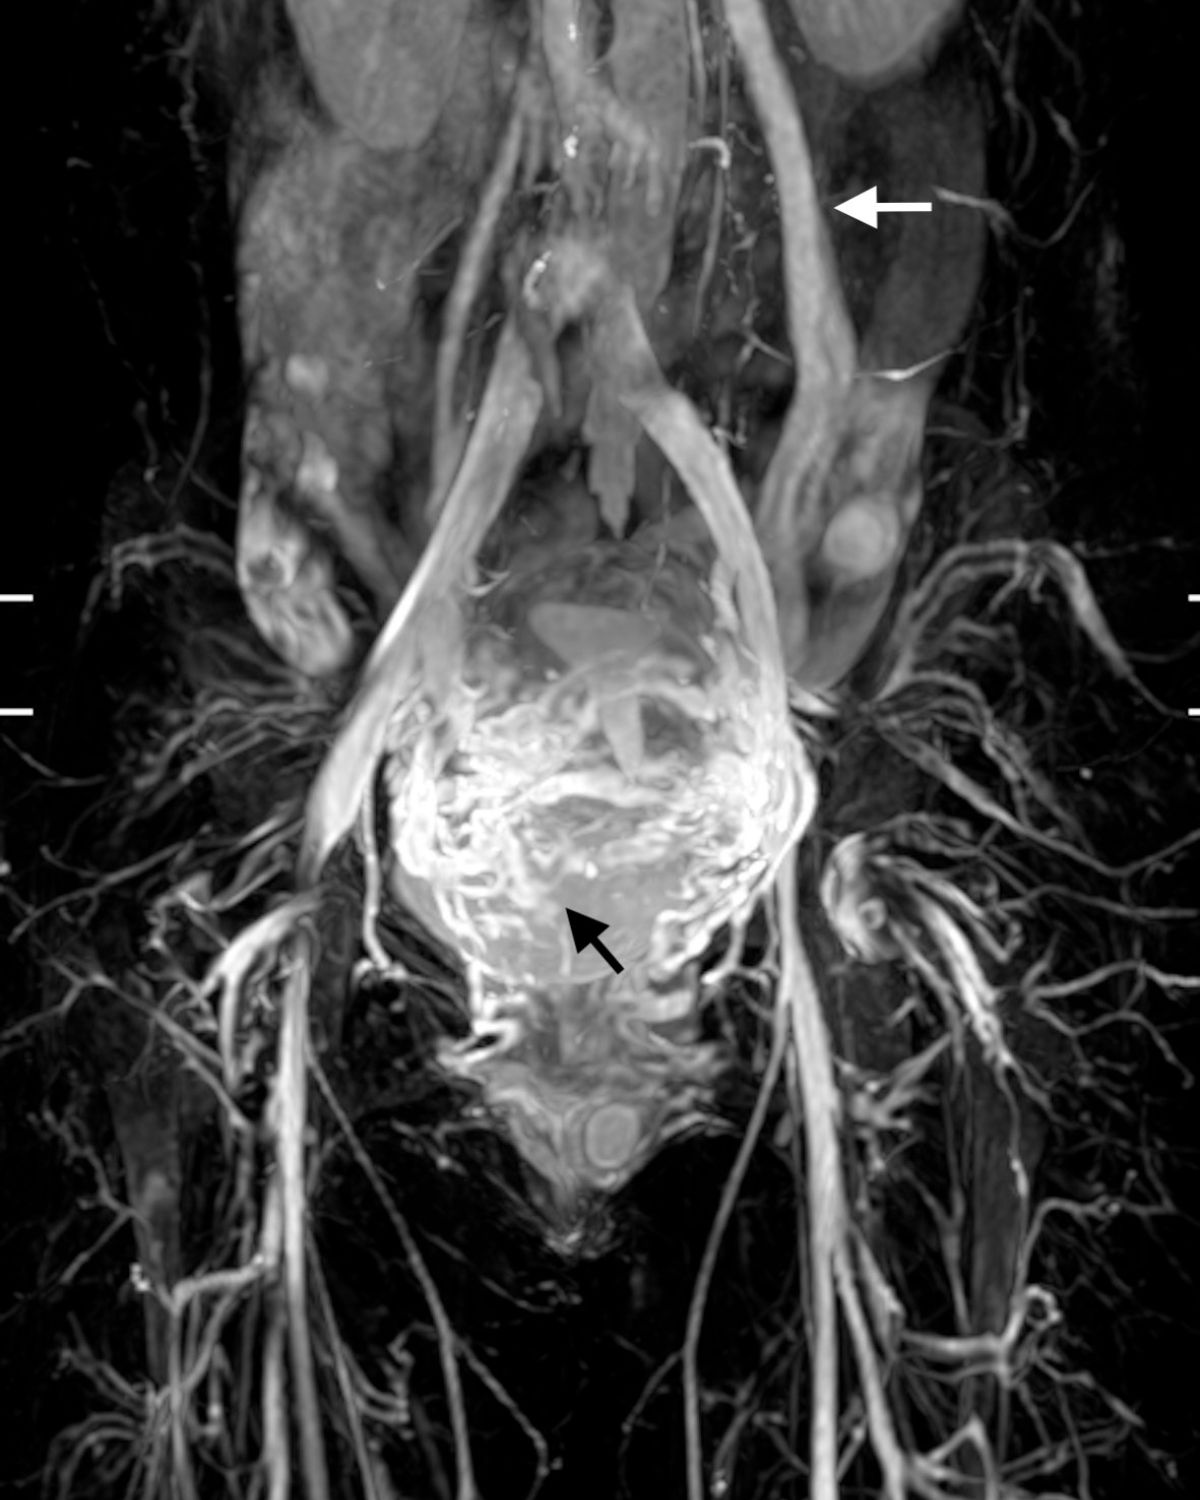

圖二:白色箭頭:擴大、逆流的左生殖靜脈 黑色箭頭:因血流過多造成的子宮靜脈曲張,常引起下腹痛

過多的骨盆腔血流也會流竄到身體的其他地方包括骨盆腔底部的會陰以及腰椎後方的血管。

在無毒核磁靜造影中,可以讓病患及醫師視察到逆流及粗大的生殖靜脈及子宮/直腸/膀胱/陰道附近的扭曲的靜脈,甚至在私密處的骨盆腔靜脈滲漏。